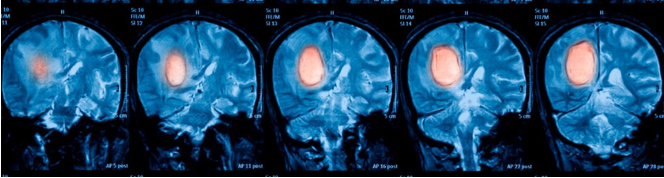

腦腫瘤是怎么樣一個(gè)發(fā)展進(jìn)程?以下兩個(gè)gif圖帶你看懂 (從左到右分別為腦腫瘤初始,1個(gè)月后,6個(gè)月后,1年后) (從左到右分別為腦腫瘤初始,4個(gè)月后,6個(gè)月后,1年后,1年半后)...

(從左到右分別為腦腫瘤初始,4個(gè)月后,6個(gè)月后,1年后,1年半后)